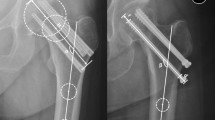

Tang et al. proposed the “triangular stability theory” of the proximal femur and pointed out that the proximal femur is stabilized by a structural mechanical model formed by the medial, lateral, and upper sides26,34. The medial side forms the oblique support of the cantilever configuration of the proximal femur, which greatly reduces the bending stress and deflection of the structure. The lateral side could significantly reduce the sliding and deflection of the femoral neck under physiological load, and achieve the stability of the fracture end. The upper side connects the medial and the lateral side which could resist the bending moment generated by the physiological load. When the femoral neck fractures, the upper and medial edges of the proximal femur were destroyed at once. The medial edge structure relies on the medial support of the femoral calcar screw to achieve reconstruction. The upper two screws in the oblique triangle configuration provide the best mechanical strength, reconstruct the upper side structure of the proximal femur, and significantly improve the mechanical stability of the fractured end. The configuration of three screws in the OTC model of femoral neck fracture was established to reduce the strain in the internal fixation component, maintain the stability of the fracture end, and promote fracture healing (Fig. 7).

According to the oblique triangle configuration, the position of the three screws on the cross-section of the femoral neck isthmus by the 3-Matic software. (a) The blue line was the contour of the femoral neck isthmus, and the yellow dashed line was the fitted ellipse of the femoral neck isthmus. (b) The configuration of the screws according to the cross-section of the FNI. (c) the OTC in anteroposterior view, (d) the OTC in lateral view.